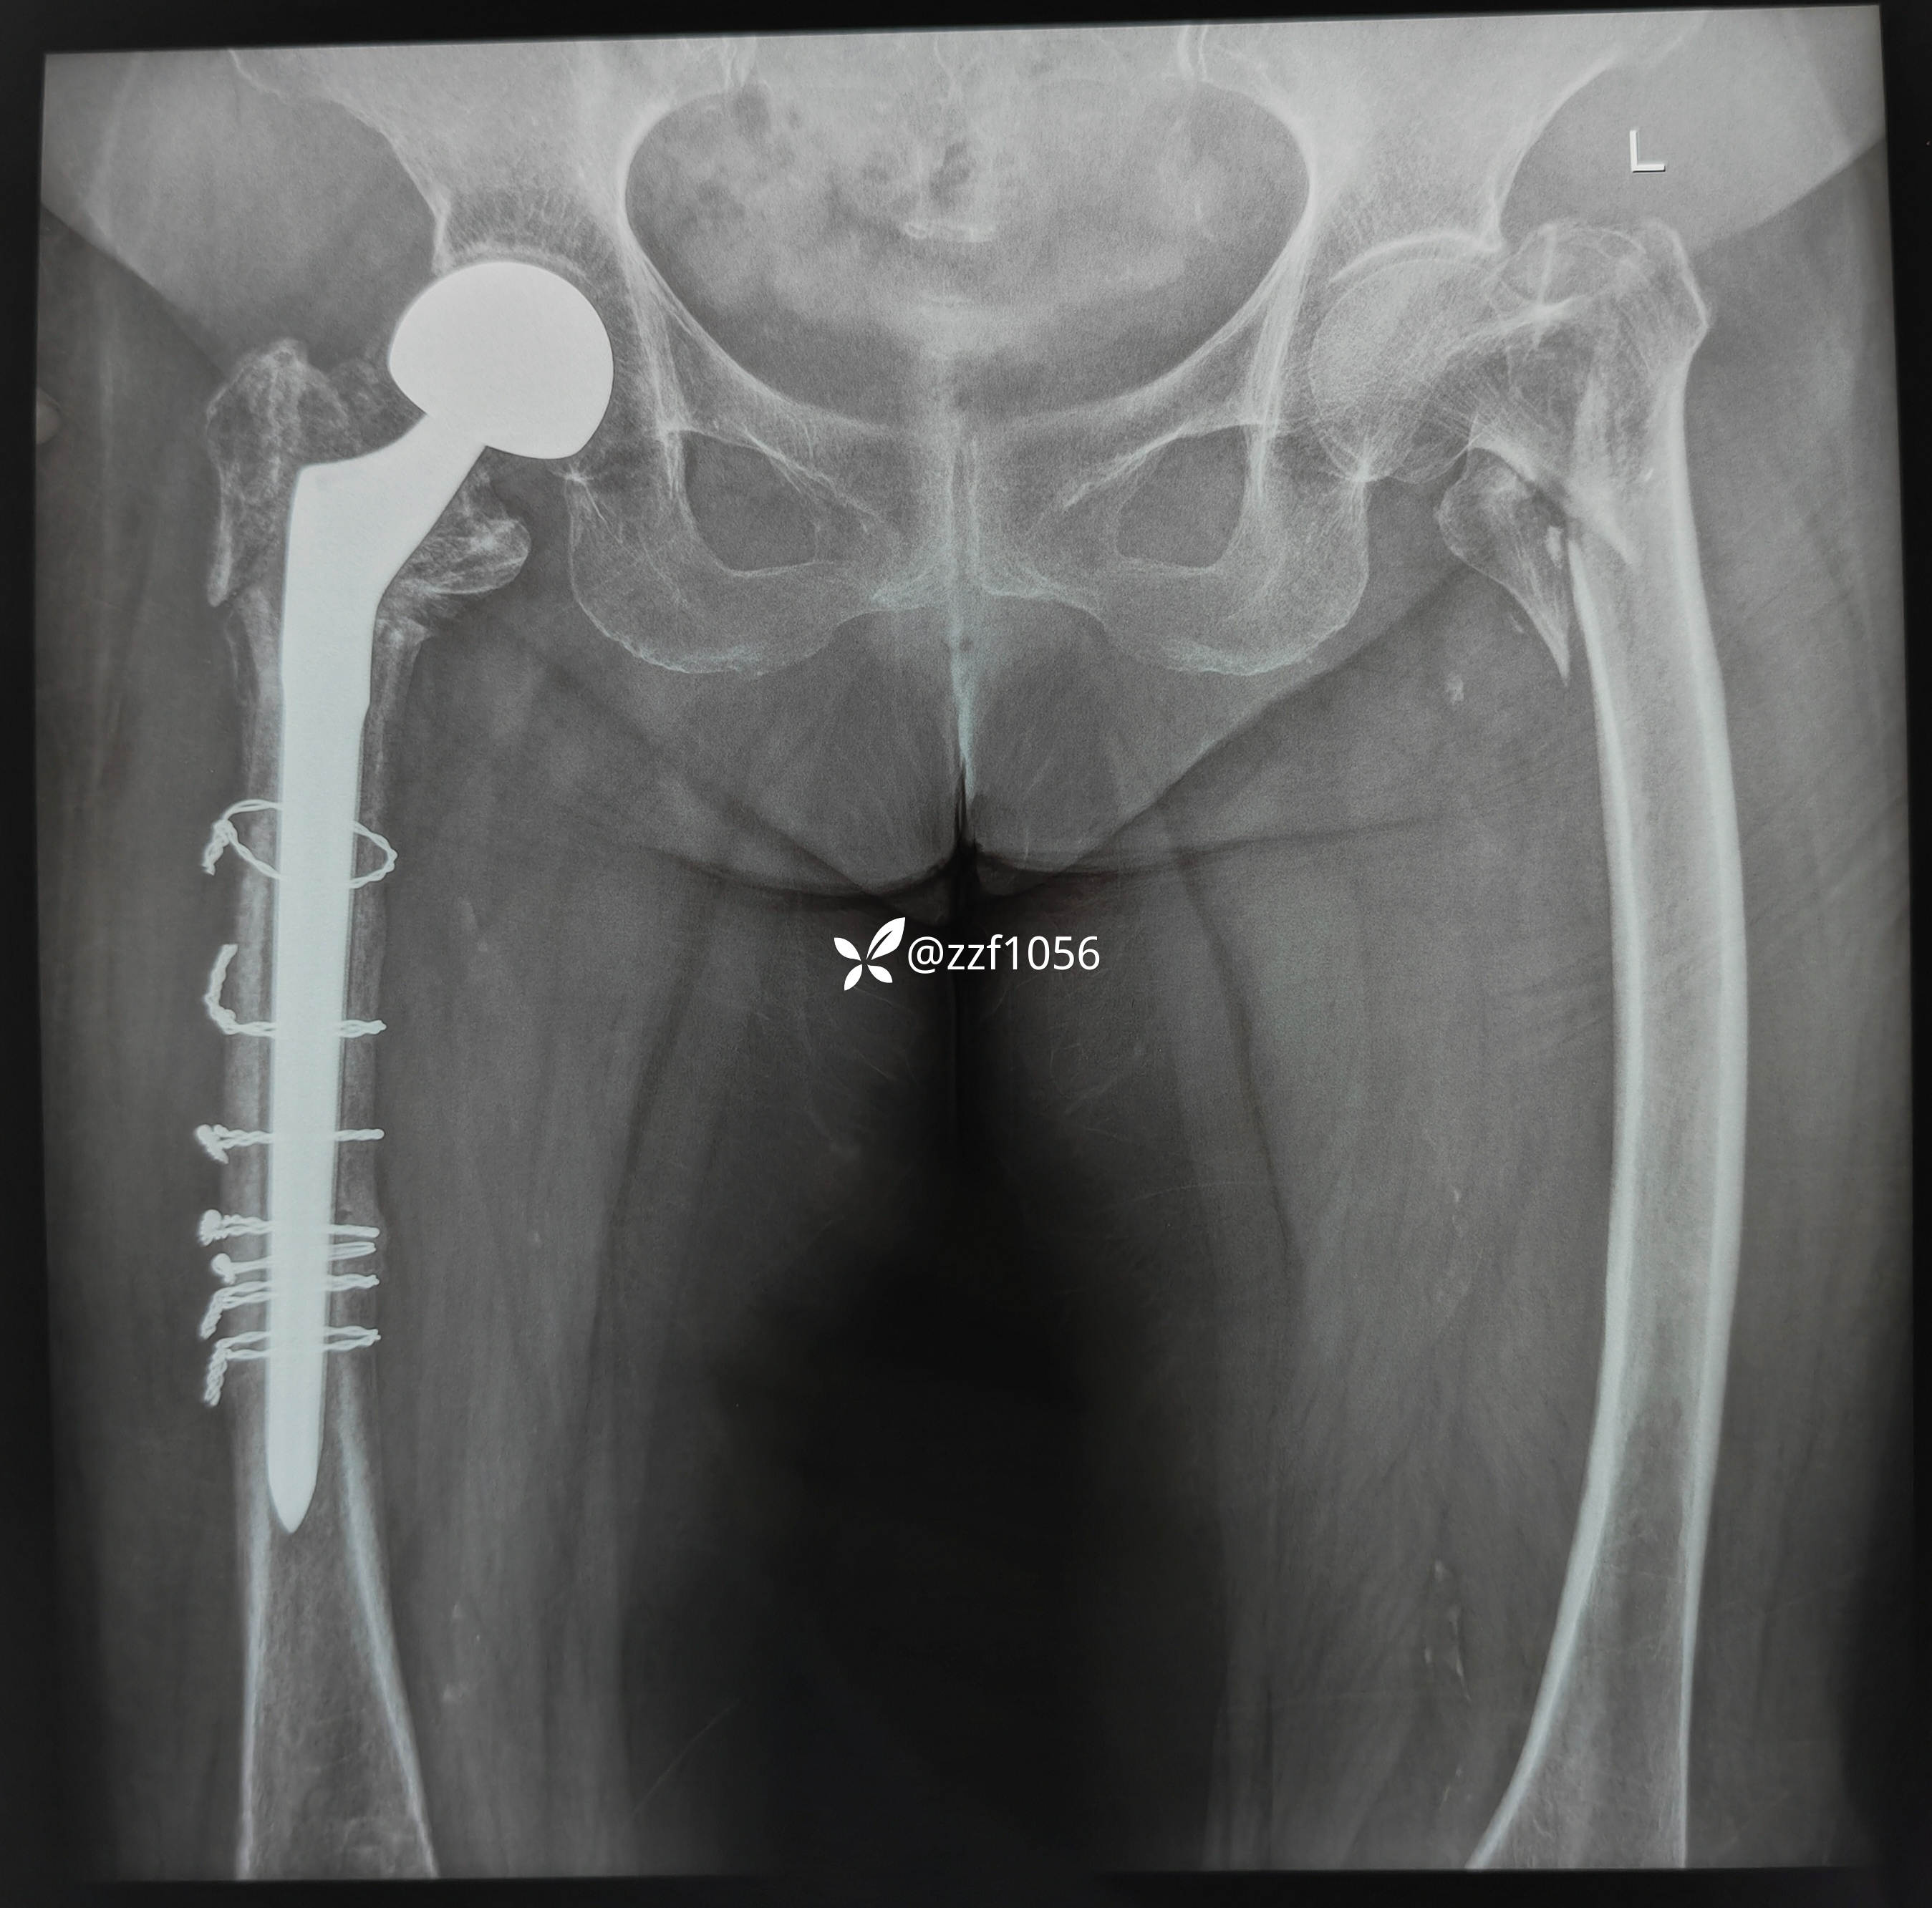

祸不单行,pfna失效,改关节置换术中股骨干再骨折,病房休克抢救,时隔四个月再次骨折

去年因摔伤致右侧转子间骨折,行Pfna固定,出院后一直未复查

术后2个月自行在家行走,不小心再次摔伤导致右髋一直疼痛

术后4个月终于来院复查,摄片显示pfna内固定失效,拒绝翻修并离院

术后4个半月考虑清楚,咨询了熟人要求髋关节置换,住院拟定全髋手术

术中去除内固定顺利,使用瓦格纳柄,术中出现插曲,出血量多和干部骨折,多处捆扎,全髋改半髋下台,😰虐心,懂得都懂

行走三个月康复良好,奈何再次摔伤,导致左侧转子间再骨折,A2.3型